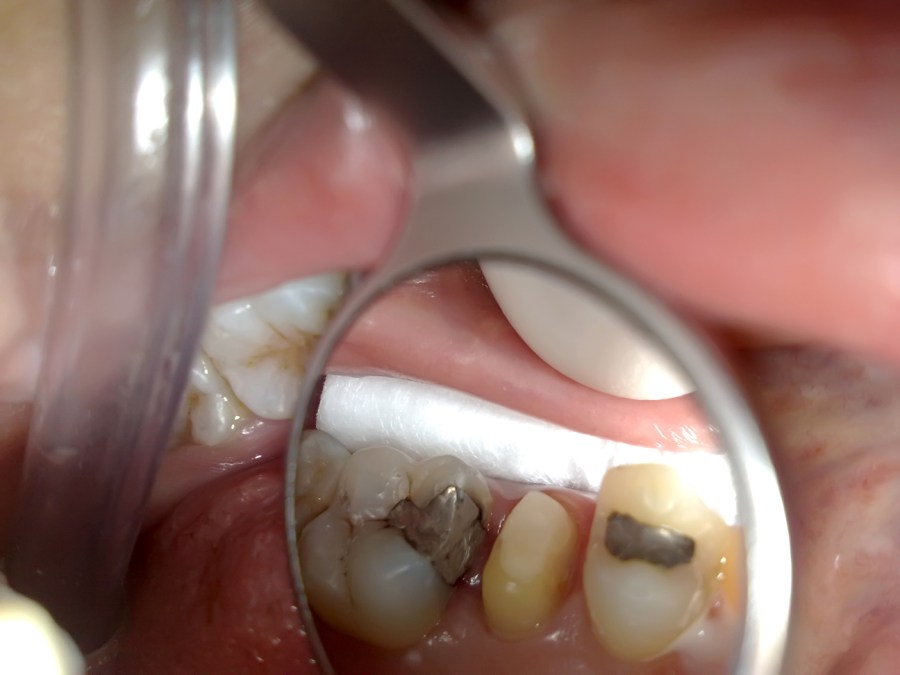

When Metal Onlay Failed and Endo Do the Rest